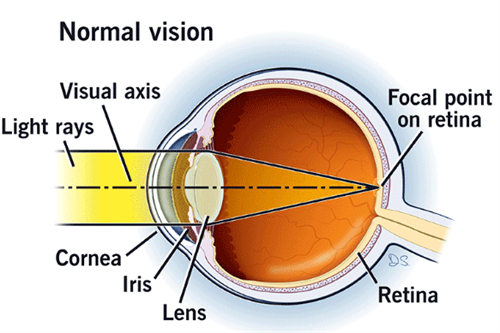

核心优势:茗视光以“比较准检查”为技术基石,其建***院区配备蔡司CLARUS 500超广角眼底相机、OCULUS Corvis® ST角膜生物力学分析仪等设备,可提前发现青光眼早期病变。

个性化小梁切除术:根据角膜生物力学数据调整手术参数,术后散光发生率降低。

青光眼引流阀动态调节术:通过智能阀门控制房水流出量,避免术后眼压波动。